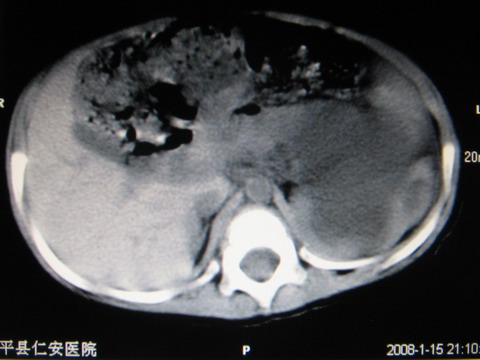

标题: PED0552:男1岁,双肾区CT [打印本页]

标题: PED0552:男1岁,双肾区CT

胎龄5个月时b超示左肾积水,现一岁后复查

左肾重度积水!

左肾重度积水!考虑肾盂输尿管交界处先天性狭窄或闭塞所导致

先天性左输尿管狭窄所致左肾重度积水。